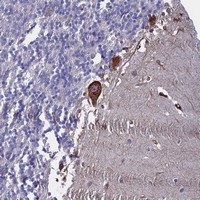

- Experimental details

- Immunohistochemical staining of human cerebellum with C11orf70 polyclonal antibody (Cat # PAB23505) shows strong cytoplasmic positivity in purkinje cells at 1:20-1:50 dilution.

- Validation comment

- Immunohistochemistry (Formalin/PFA-fixed paraffin-embedded sections)